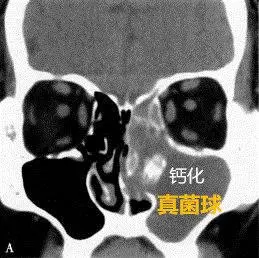

真菌性鼻窦炎有哪些症状,怎么治疗?